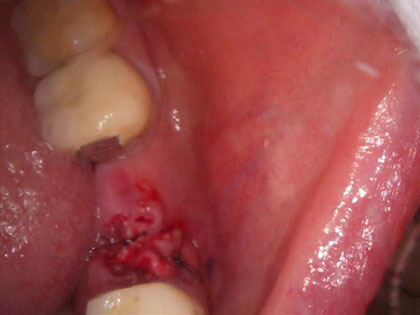

• 治療中の写真がこちら

• インプラント治療中2

• 抜歯時に骨造成を同時に行い、そこから4か月後にインプラントを埋入しました。